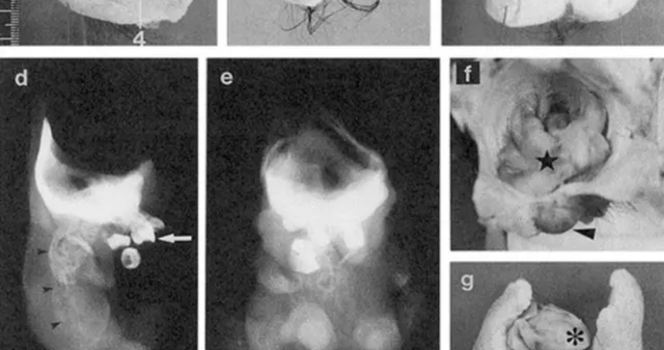

Brzmi jak scena z filmu grozy, ale to rzadki i opisany w literaturze medycznej przypadek. Podczas operacji guza jajnika u 25-letniej pacjentki w Japonii lekarze natrafili na niezwykle nietypową postać potworniaka: wewnątrz znajdowała się zorganizowana struktura z „głową, tułowiem i kończynami” – na tyle przypominająca miniaturową postać, że w publikacjach popularnonaukowych zaczęto o niej pisać jak o „lalkowym ciele”.

W opisie przypadku, opublikowanym w bazie National Library of Medicine, autorzy wskazują, że była to dojrzała postać fetiform teratoma (bywa też określana jako „homunculus”) – bardzo rzadki wariant potworniaka, w którym tkanki różnicują się w sposób wyjątkowo uporządkowany.

Badanie mikroskopowe potwierdziło obecność wielu typów tkanek, m.in. struktur oka, ucha, zębów, kości i szpiku, fragmentów przewodu pokarmowego i tchawicy, a także tkanki nerwowej opisywanej jako elementy mózgu/układu nerwowego.

Ten przypadek jest inny, bo autorzy opisują, że struktura miała wyraźnie zaznaczone osie „przód-tył” i „lewo-prawo” oraz układ, który przypominał elementy anatomiczne ułożone „sensownie” w przestrzeni. To właśnie sprawia, że fetiform teratoma bywa porównywany do „mini-ciała”, choć wciąż jest to guz, a nie rozwijający się płód.